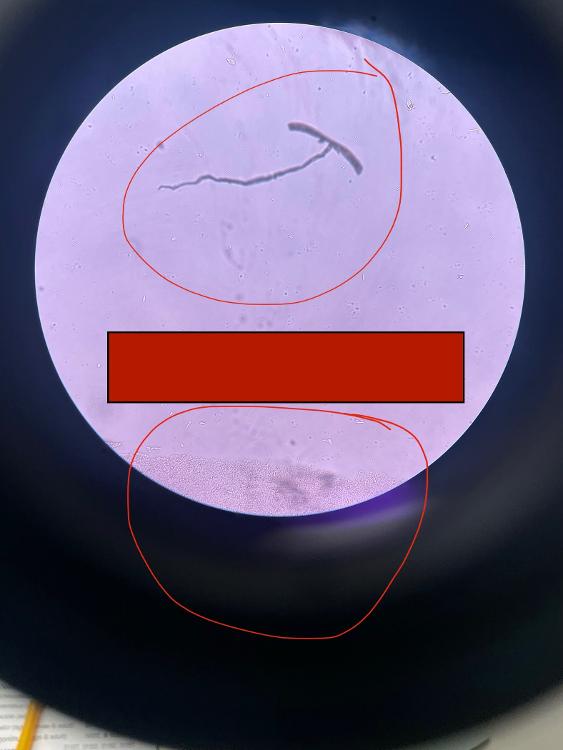

Trypanosoma gambeinse (blood smear)